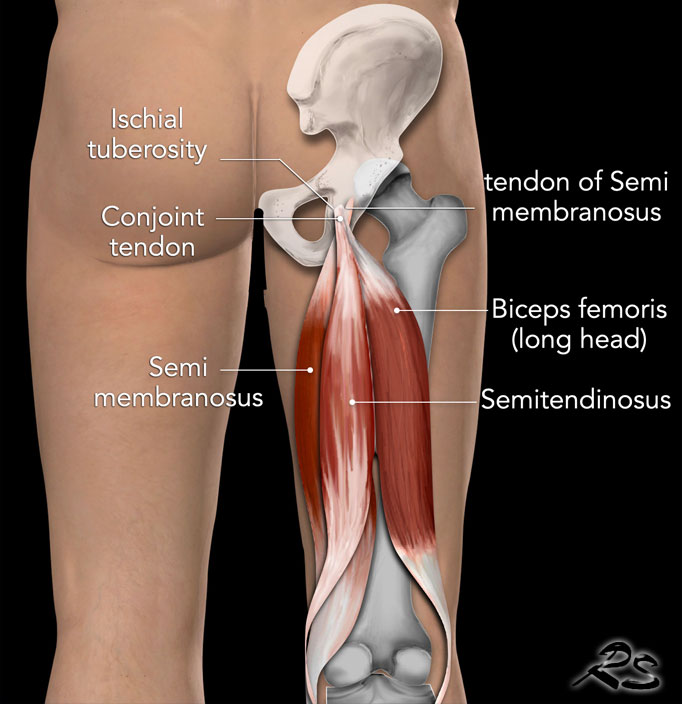

Il complesso del tendine del ginocchio è costituito da tre muscoli primari: il semimembranoso, il semitendinoso e il bicipite femorale (che ha teste sia lunghe che corte). Questi muscoli originano dall'aspetto posterolaterale della tuberosità ischiatica. In particolare, il bicipite femorale e il semitendinoso condividono un'origine tendinea congiunta, che si trova posteromedialmente all'origine del semimembranoso. L'impronta del tendine semimembranoso è posizionata leggermente anterolateralmente.

Il tendine congiunto misura circa 10 cm di lunghezza e corre tra il bicipite femorale, il capo lungo e il ventre del muscolo semitendinoso. Il capo lungo del bicipite femorale nasce dalla tuberosità ischiatica, appena distale al muscolo semitendinoso. Il bicipite femorale a testa corta ha un'origine più distale separata dalla linea aspera, una cresta sul femore posteriore. Queste origini distinte contribuiscono a diverse funzioni: la testa lunga è responsabile sia dell'estensione dell'anca che della flessione del ginocchio, mentre la testa corta flette principalmente il ginocchio.

Il tendine semimembranoso è il più lungo dei tendini prossimali del tendine del ginocchio, misurando circa 30 cm di lunghezza. Mentre scende, si appiattisce e si trova anteriormente al ventre del muscolo semitendinoso, posteriormente al muscolo magnus adduttore e medialmente al nervo sciatico. Il muscolo semimembranoso prossimale ha origine come un piccolo muscolo di forma triangolare dall'aspetto mediale di questo tendine appiattito. Quando il muscolo semimembranoso si estende caudalmente, si allarga e ha la più grande area della sezione trasversale dei muscoli posteriori della coscia, consentendogli di generare la massima forza.6

Il tendine semimembranoso distale ha più inserzioni, anche lungo la tibia prossimale posteromediale e altri componenti dell'angolo posteromediale del ginocchio. Il muscolo semitendinoso termina nel terzo distale della coscia, formando un lungo tendine distale che si attacca all'aspetto anteromediale della tibia prossimale, contribuendo al complesso del piede anserina insieme ai tendini del gracile e del sartorio.